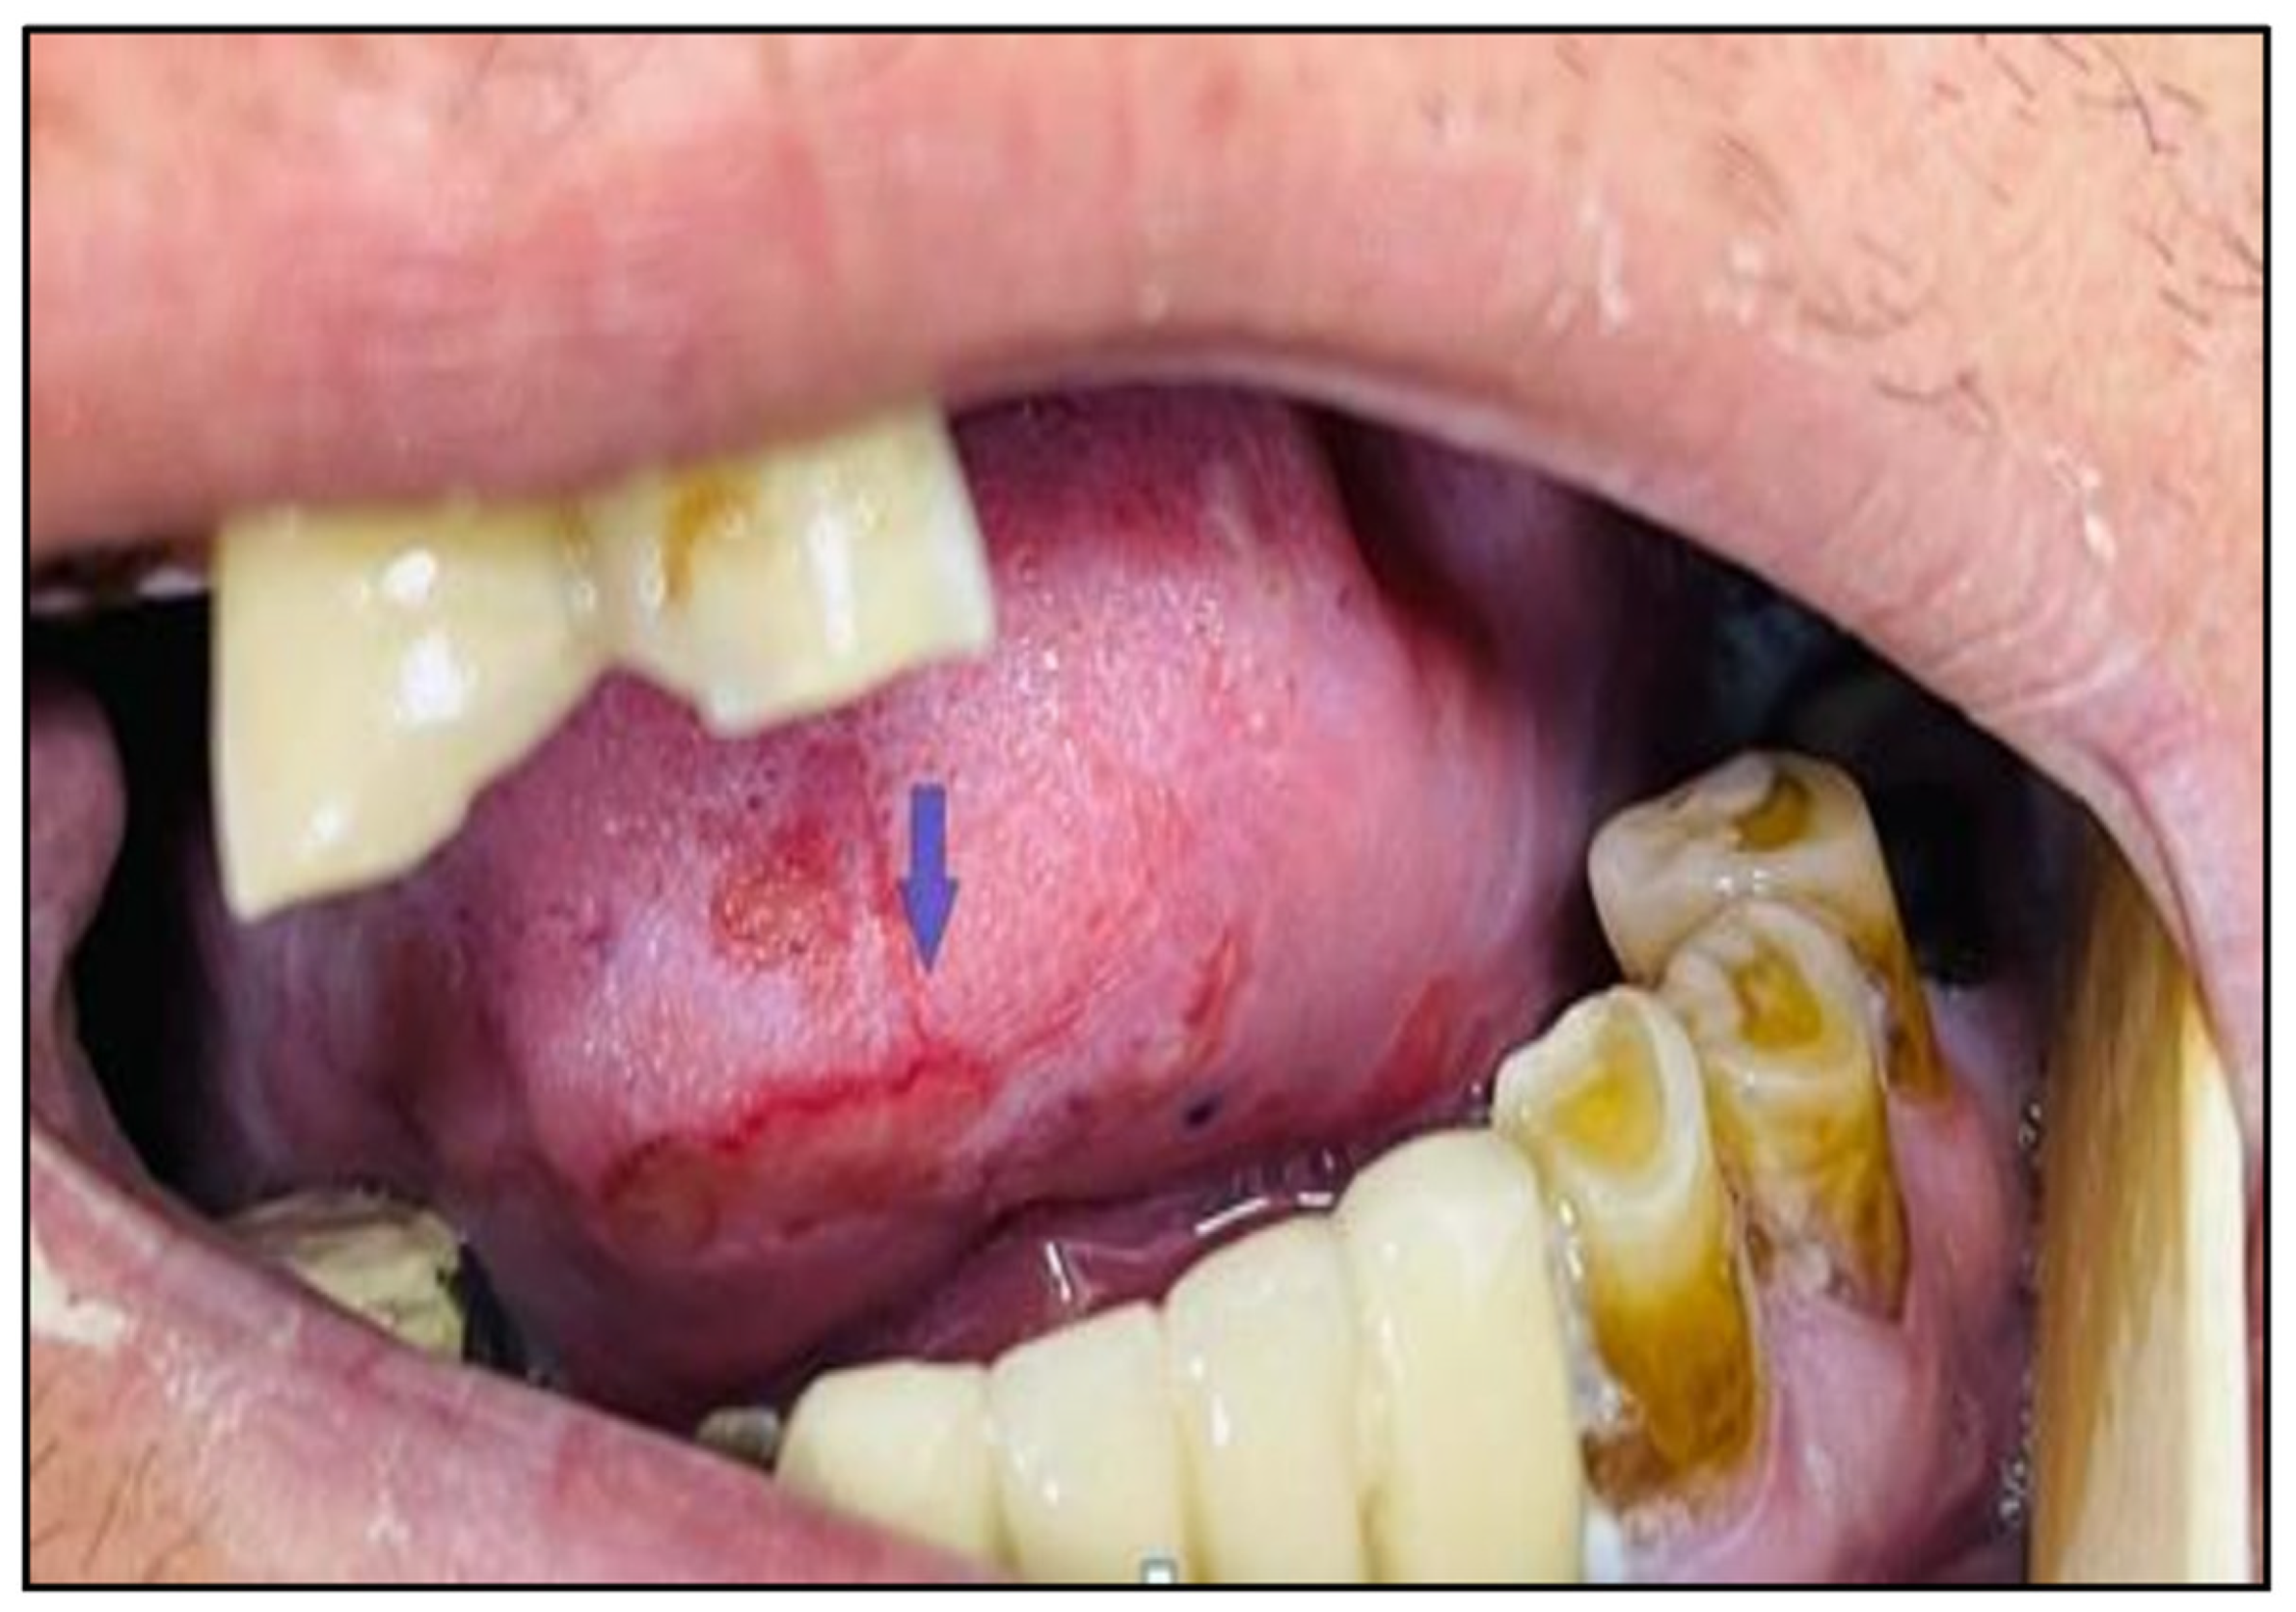

Five phases can be used to summarise the pathophysiology of OM: initiation of tissue injury, upregulation of inflammation via generation of messenger signals, signaling and amplification, ulceration and inflammation, and healing [27]. The main clinical presentation of OM (Figure 3) is pain accompanied by a burning sensation, usually aggravated by hot or spicy foods. Erythema, mucosal atrophy, and ulcerations with or without white pseudomembranes are additional signs [8,9]. Individuals with HNC who receive chemotherapy in addition to RT have an increased chance of developing OM that is more severe and lasts longer than that due to RT alone. Also, patients 65 and older have a higher grade (3–4) OM than younger patients during RT [9]. Other factors that may impact the severity of OM include RT dose, chemotherapy dose and type, poor oral hygiene, local irritants (like tobacco and alcohol), and the patient’s overall health status [28]. The most commonly used scale to evaluate OM is the one that was reported by the World Health Organization (WHO), which classifies OM into four grades [9] (Table 1). The prevalence of RT-related OM ranges from 36% to 100% of patients [11], and very few patients may finish their treatments without getting OM [29]. In most cases, OM begins during the 2nd or 3rd week of RT initiation and may vanish after 8 to 10 weeks of RT completion, depending on its severity [25,30]. The prophylactic measures of OM may include maintaining good oral hygiene with frequent teeth cleaning and daily mouth rinses (by salt and sodium bicarbonate or diluted hydrogen peroxide solution), systemic supplements such as oral glutamine and oral zinc, low-level laser therapy, and using mouthwashes containing zinc sulfate or polyherbal contents (including chamomile, peppermint oil, Aloe vera, and honey) which may be effective in preventing severe grades of OM and its related pain [8,9,11]. The main goal of OM treatment is soothing and symptomatic. Different therapies can be used during OM incidence, like palifermin injections, benzylamine hydrochloride oral solutions (can alleviate pain), local antihistamine rinse (such as Benadryl elixir), coating agents (MuGard, Maalox, or Sucralfate solutions), topical anesthetics (like 2% viscous lidocaine or tetracaine-chloride), and chlorhexidine mouthwash (reduces the risk of oral infection). Topical analgesics such as morphine (0.2%) and doxepin (0.5%) mouthwashes for mild-moderate cases, but severe cases may need systemic analgesics. Also, using low-level laser therapy during RT effectively reduces the severity of RT-related OM and controls manifestations [8,9,11,24,27,30,31]. Lifestyle measures can be followed in mild degrees of OM to reduce the OM pain and maintain the patient with adequate nutritional status, such as eating small, divided (4–6) meals rather than big three meals and taking easy-to-swallow nutritional kinds like soups and milkshakes [30].

Figure 3.

Oral mucositis (ulcerations with pseudomembrane in the lateral and internal surfaces of the tongue) in a male patient with HNC after RT completion.